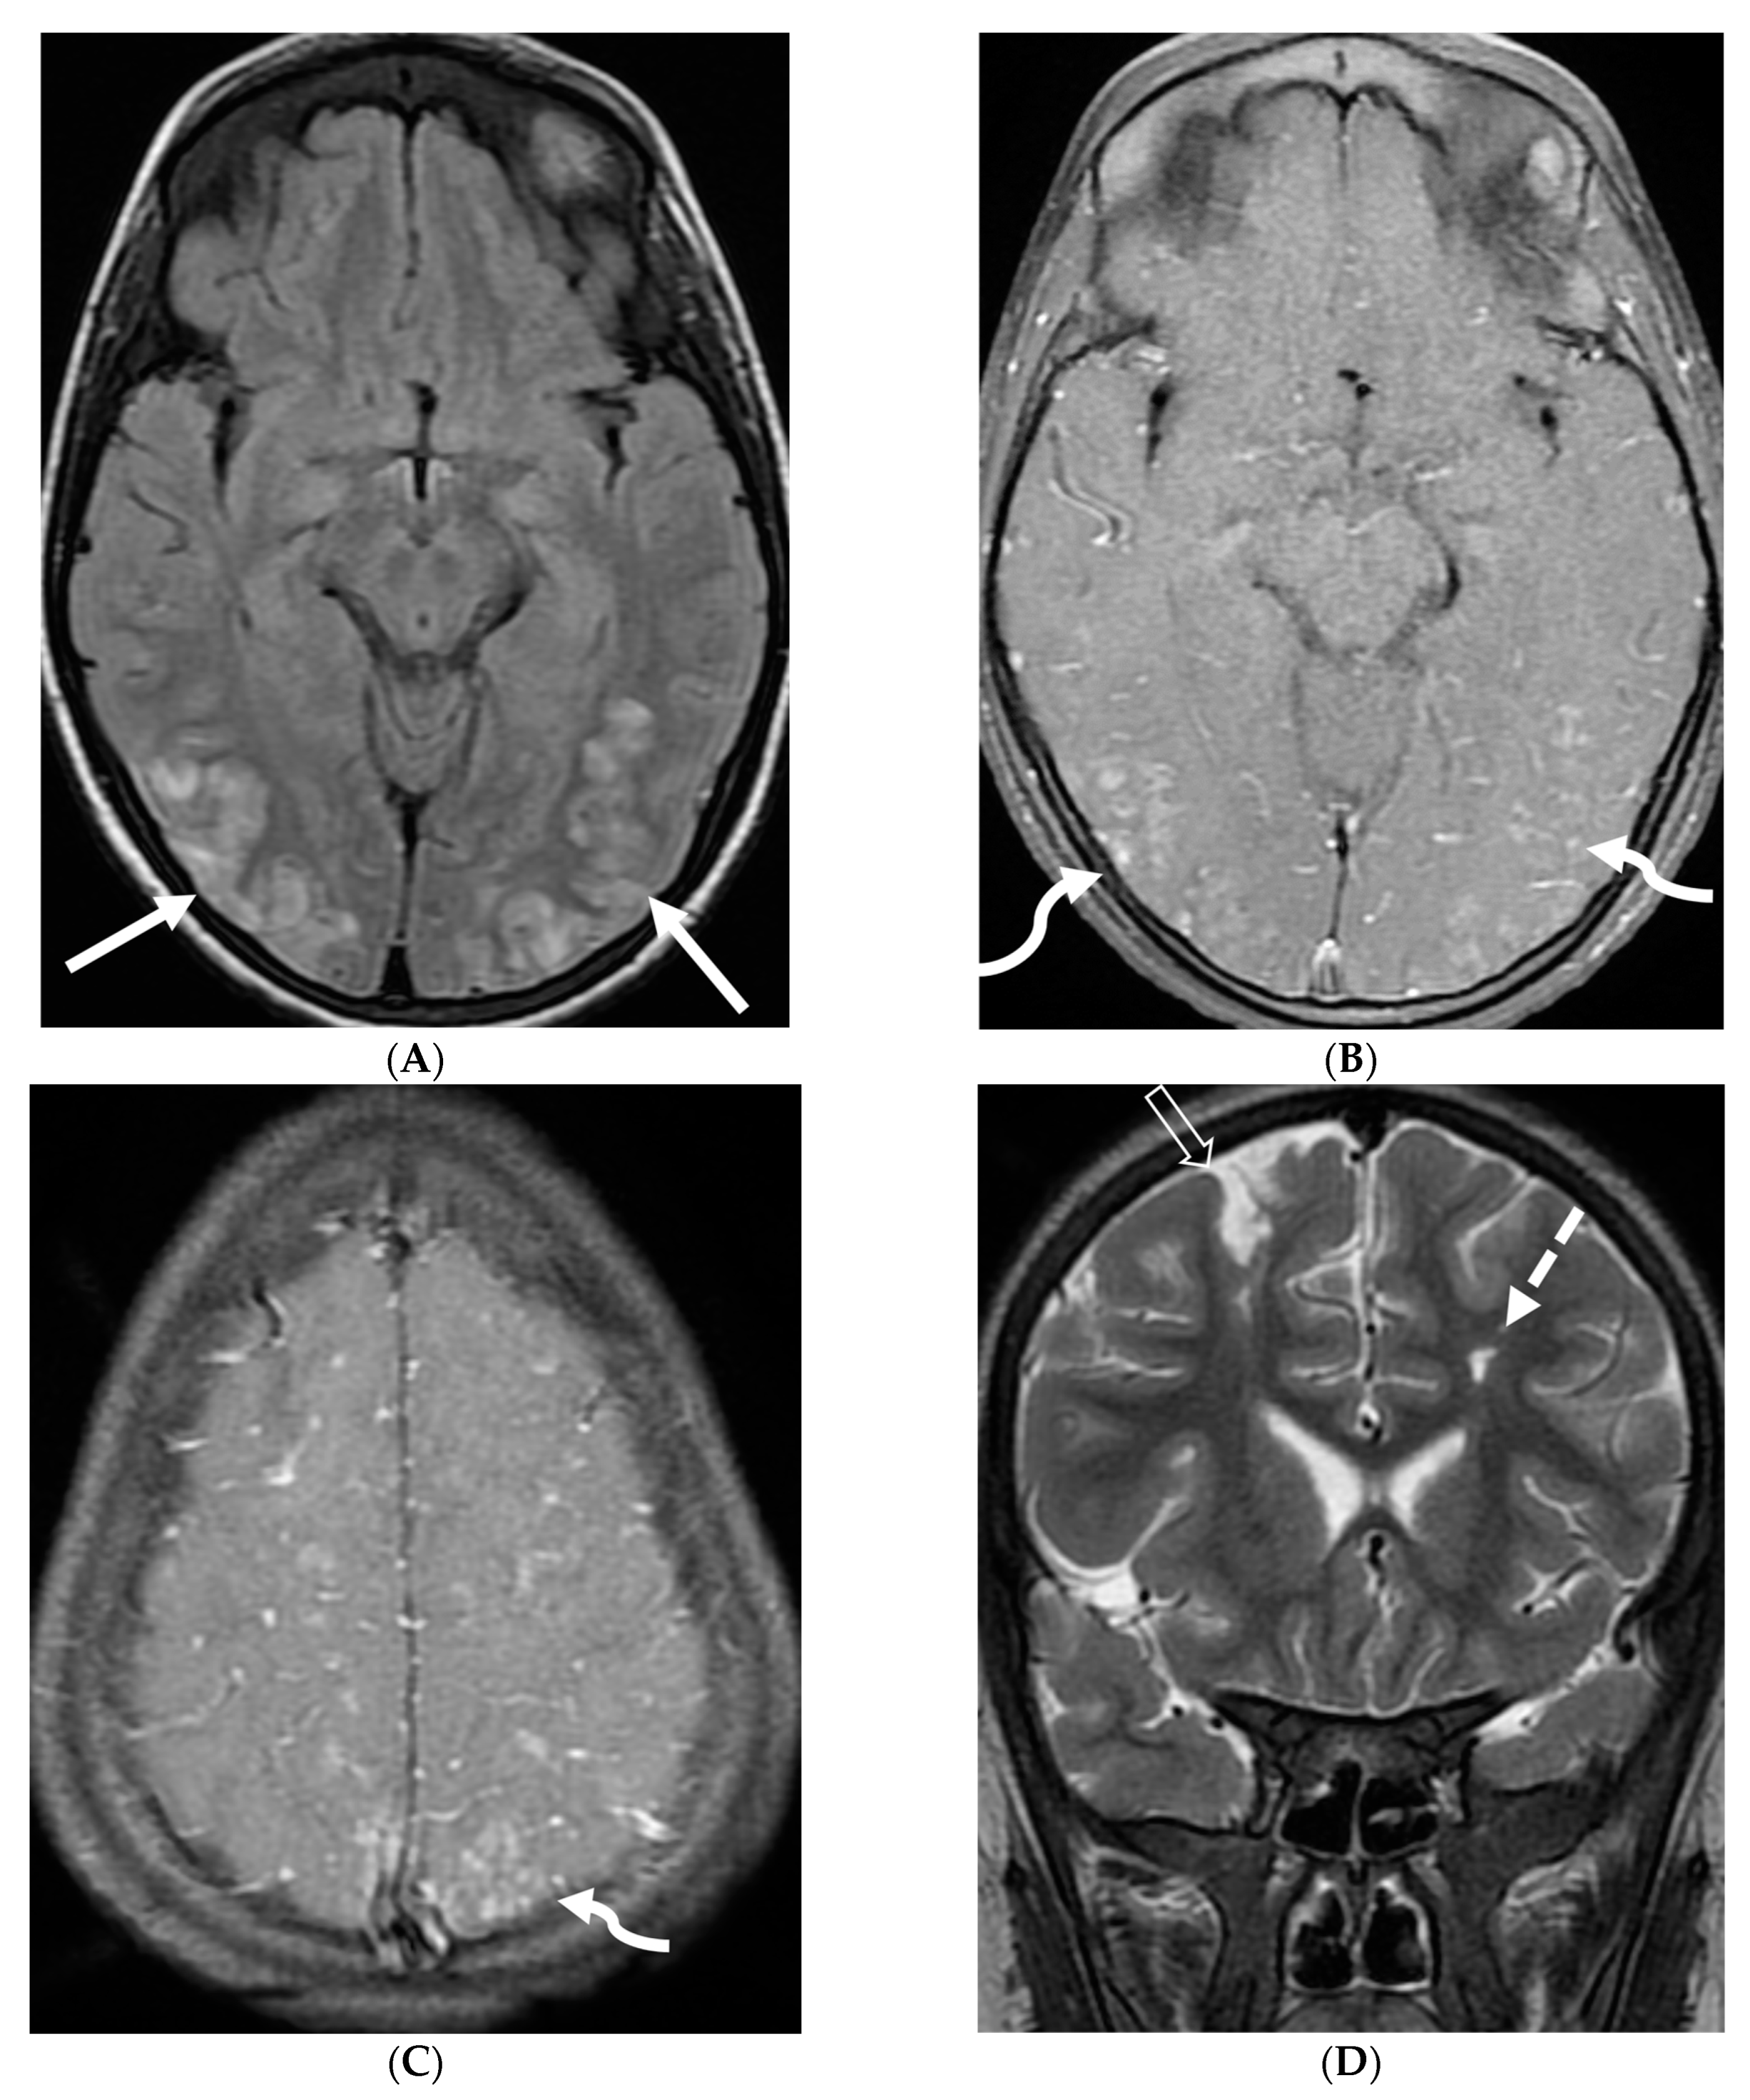

3.7. Primary Leptomeningeal Rhabdomyosarcoma

Rhabdomyosarcoma, the most common childhood soft tissue sarcoma, is commonly seen in the head and neck, genitourinary tract and extremity [58]. Primary meningeal rhabdomyosarcoma is extremely rare [59,60]. It is hypothesized that the origin of this rare variant is cerebral parenchyma with secondary leptomeningeal spread [61].

Diffuse LME with areas of leptomeningeal thickening and nodularity would be the prominent imaging finding which may cause hydrocephalus. These findings mimic more common entities such as infection (e.g., tuberculosis) or inflammation (e.g., neurosarcoidosis).

Marked focal nodularity and mass effect causing a deformed contour on the spinal cord favor a neoplastic process (Figure 7) [62]. Accurate staging is crucial as the presence of leptomeningeal or multifocal disease have implications on radiotherapy fields and total dose. Additionally, PET-CT scan assists in evaluating for an extracranial primary site [63].

Figure 7.

3-year-old boy with 2 weeks history of headache and vomiting. Axial FLAIR (A), post contrast axial T1 FS (B) and sagittal 3D inversion recovery (C) images demonstrate FLAIR hyperintensity in the interpedencular cistern (curved arrow) and mild hydrocephalus. Extensive meningeal enhancement most prominent at the skull base, basal cisterns, and Sylvain fissures (arrows), but extending throughout the brain. There is meningeal enhancement, with coating of the brainstem extends inferiorly along the cervical spinal cord (dashed arrows). Sagittal T2 (D), sagittal T1 (E) and fat saturated T1 post (F) images show extensive leptomeningeal with predominantly solid and some cystic nodules (curved arrows) on T2 sequence and isointense on T1 (arrows). Lesions predominantly involve the posterior spinal canal, causing mass effect and anterior displacement of the spinal cord. The solid nodules show enhancement after contrast injection and extensive uniform diffuse LME around the cord (dashed arrows). Pathology: Primary Meningeal Rhabdomyosarcoma.